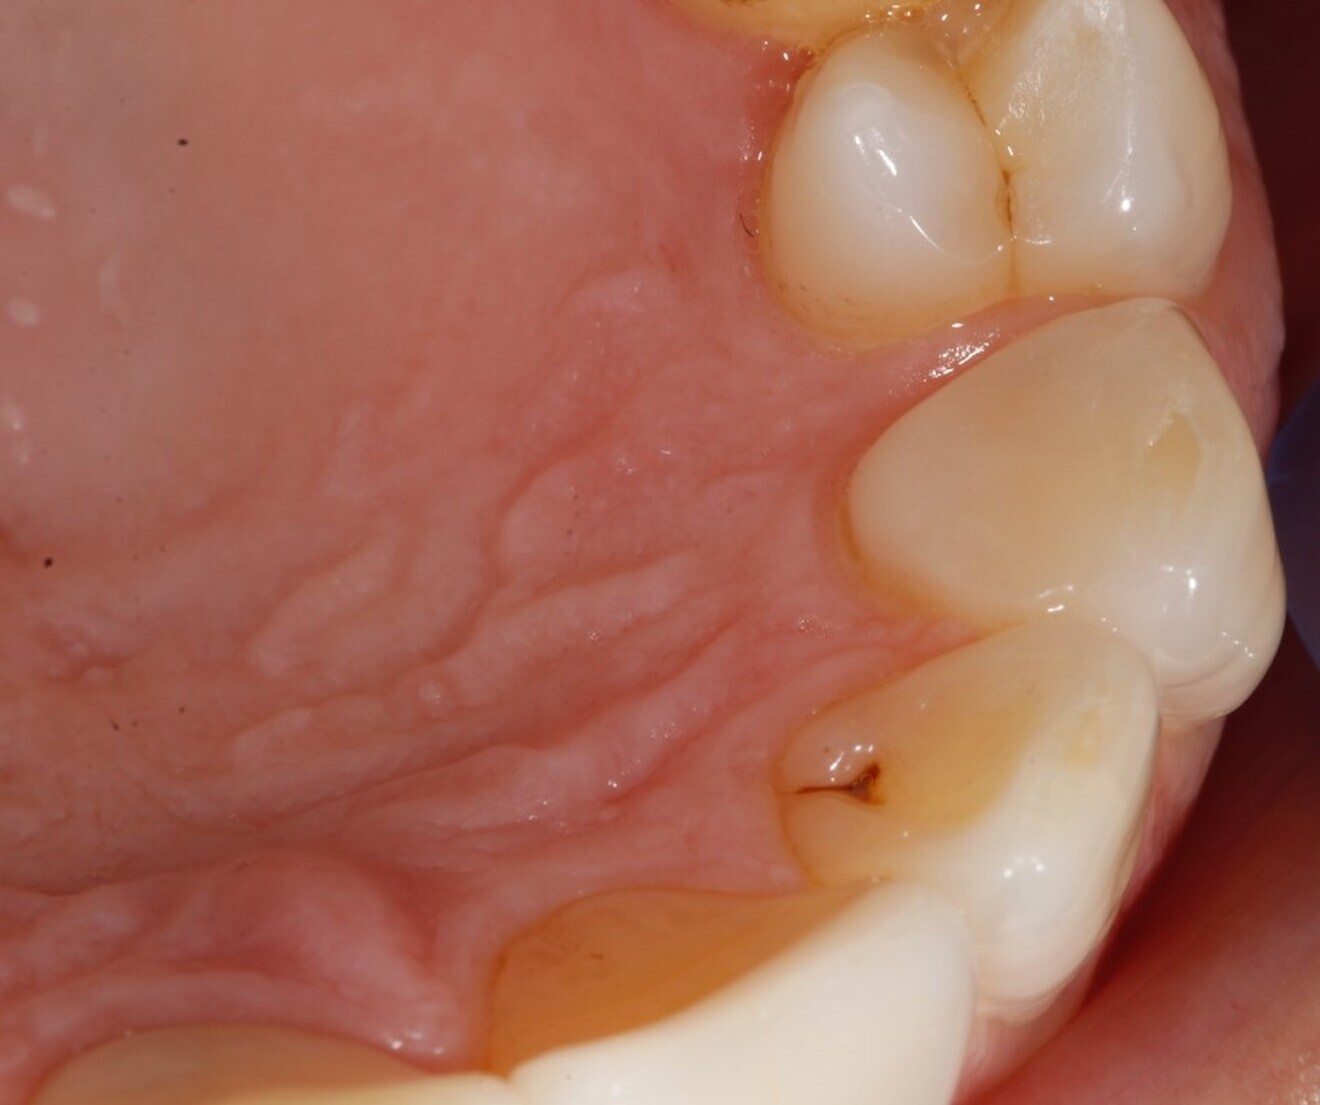

In 2021, the patient decided to have the two maxillary central incisor restorations replaced with a lithium disilicate crown and veneer (Fig. 13). The maxillary palatal platforms created with Venus Diamond in 2017 were still functional, and the repaired mandibular central incisal edge was still intact (Figs. 14 & 15). The original edge bonding on the other mandibular teeth still remained in place, 17 years later.

Fig. 14: 2021—the repaired mandibular central incisal edge still intact.

Fig. 15: 2021—the maxillary palatal platforms created with Venus Diamond still functional.